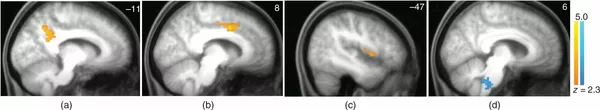

Безобразная Эльза Опубликовано 9 января, 2020 Опубликовано 9 января, 2020 В отключке. Что происходит с мозгом йогов и шаманов 08:00 05.01.2020 (обновлено: 08:10 05.01.2020) 10681 © РИА Новости / Екатерина Чеснокова Перейти в фотобанк МОСКВА, 5 янв — РИА Новости, Татьяна Пичугина. Йоги лучше управляют эмоциями, менее подвержены стрессу, дольше сохраняют мыслительные способности. Медитация, как и шаманский транс, включают в мозге нейронную сеть, вводящую человека в состояние отрешенности и озарений. К такому выводу ученые пришли, анализируя экспериментальные данные. Как мозг уходит в себя Йога, зародившаяся в Индии более двух тысяч лет назад, призвана помочь человеку достичь гармонии тела и духа. На Западе йога тоже очень популярна, поэтому ученые не испытывают недостатка в добровольцах для опытов, а функциональная МРТ дает большой фактический материал об активности тех или иных отделов мозга прямо во время занятий. Одно из последних открытий — сеть пассивного режима (default mode network). Это крупная нейронная структура, связывающая разные участки мозга. Активизируется, когда человек уходит в себя, отключается от внешнего мира. В принципе, люди полжизни проводят в таком состоянии. Но к нему ведет и осознанная медитация. Чтобы глубже изучить пассивный режим мозга, ученые из Германии и Испании пригласили новичков пройти 40-дневный интенсивный тренинг по медитации. До и после эксперимента мозг сканировали, чтобы картировать активные участки по приливу к ним крови, насыщенной кислородом. Это БОЛД функциональная МРТ с регистрацией амплитуды низкочастотных флуктуаций, позволяющая исследовать мозг во время отдыха. 6 сентября 2017, 14:39 Ученые доказали, что йога и медитация улучшают работу мозга После тренинга у всех добровольцев обнаружили утолщение левого предклинья. Этот участок находится в теменной области коры и задействован в нейросети пассивного режима. В то же время амплитуда низкочастотных флуктуаций там снизилась, а сами люди отметили ослабление симптомов депрессии и стресса. Йога также усиливает связную работу мозга. Это показали ученые из Бразилии и США, наблюдавшие три группы женщин возрастом старше 60 лет. Первая — с многолетним опытом медитаций, вторая — начинающие, третьи ничем подобным вообще не занимаются. Все прошли МРТ, заполнили анкеты. Выяснилось, что у опытных йогов сеть пассивного режима действует гораздо эффективнее. И мыслительные функции у них сохранились лучше. Авторы работы сделали вывод, что йога — перспективный метод антивозрастной терапии. © Фото : Yang, C., Barrós-Loscertales, A., Li, M. et al. Alterations in Brain Structure and Amplitude of Low-frequency after 8 weeks of Mindfulness Meditation Training in Meditation-Naïve Subjects. Sci Rep 9, 10977 (2019) Желтый — утолщение левого предклинья, красный — левой верхней теменной доли у участников тренинга по медитации. Эти участки входят с нейронную сеть пассивного режима работы мозга Шаманы помогают постичь тайны мозга Ученые Института изучения мышления и мозга Макса Планка и Медицинской школы Гарварда пригласили 15 опытных шаманов из Германии и Австрии поучаствовать в эксперименте. В течение восьми минут добровольцы слушали в наушниках с закрытыми глазами ритмичные удары бубнов, а их мозг сканировали и делали электроэнцефалограммы (ЭЭГ). Всего состоялось четыре сеанса, шаманы периодически впадали в транс. Выяснилось, что в этом состоянии усиливается взаимодействие тех участков мозга, которые входят в нейросеть пассивного режима, — речь прежде всего о задней поясной извилине коры (особенно предклинье). К ней подключались передняя поясная извилина и островок, отвечающий за стабильность функционирования мозга. Отделы, обрабатывающие звуки, наоборот, отключались. Такая перестройка нейронных сетей позволяет организовать поток внутренних мыслей, отчего и возникают озарения, полагают авторы статьи. © Фото : Oxford University Мозг в состоянии транса. Активируется совместная работа трех хабов пассивной нейросети: задней поясной извилины коры (a), передней части поясной извилины, отвечающей за когнитивную работу (b), левой передней части островка (c). Нижняя часть моста ствола мозга, наоборот, отключается от хабов Вот какой пример приводят ученые из Канады и Франции, исследовавшие француженку Корин Сомбрюн (соавтора статьи). Она родилась в Буркина-Фасо и пережила в детстве клиническую смерть. Изучала музыку и искусство, работала корреспондентом "Би-Би-Си". Снимая репортаж в Монголии, Корин непроизвольно испытала транс под звуки бубна, не могла контролировать свои движения. Местные старейшины пригласили ее на тренинг, и после восьми лет обучения она стала первой европейкой, достигшей статуса удган — женщины-шамана в монгольской традиции. Сделав ей ЭЭГ мозга и электро-магнитную томографию, ученые заключили, что транс — это не патологическое состояние. Его нельзя свести к психозу. В трансе правое полушарие доминирует над левым, которое обычно управляет мозгом. А еще происходит сдвиг от передней префронтальной к задней соматосенсорной системе, отвечающей за органы чувств. © https://doi.org/10.1080/23311908.2017.1313522 По мнению ученых, транс — это не патологическое состояние, а более углубленное погружение в себя В начале 2000-х под руководством Валентины Харитоновой из Института этнологии и антропологи РАН запустили междисциплинарный проект по изучению шаманизма и вообще измененных состояний сознания. В частности, мозг шаманов во время транса обследовали в лаборатории Нины Свидерской в Институте высшей нервной деятельности РАН. Установлено, что в обычном состоянии в мозге доминируют передние доли левого полушария и задние — правого. Они разделены условной диагональю — "когнитивной осью". В трансе, во время творческой работы или специальных дыхательных упражнений происходит переключение: возбуждаются передние доли правого полушария и задние — левого. Условная диагональ становится "осью сверхсознания". А еще в измененном состоянии сознания активируются зрительные участки мозга, поэтому человек видит вспышки света.